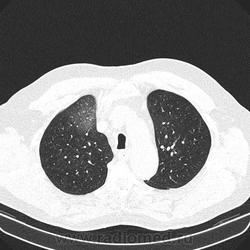

Альвеолярное кровоизлияние.

Полисегментарная пневмония.

оказалось ТЭЛА.

эту пневмонию вылечили, через некоторое время пациент поступил с подобной картиной в другом легком.

потом нашли тромб в артериях н/конечностей.